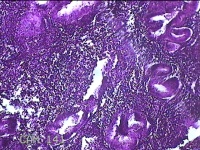

宫腔赘生物

性别

女

年龄

50岁

临床诊断

异常子宫出血 子宫腔赘生物待查 子宫肌瘤 疤痕子宫

一般病史

不规则流血25天,增多7天。

标本名称

大体所见

灰白粉红色肿物1x0.8x0.2cm两个,表面光滑。

子宫内膜增生症。制片欠佳。

增殖性子宫内膜,局部呈息肉改变